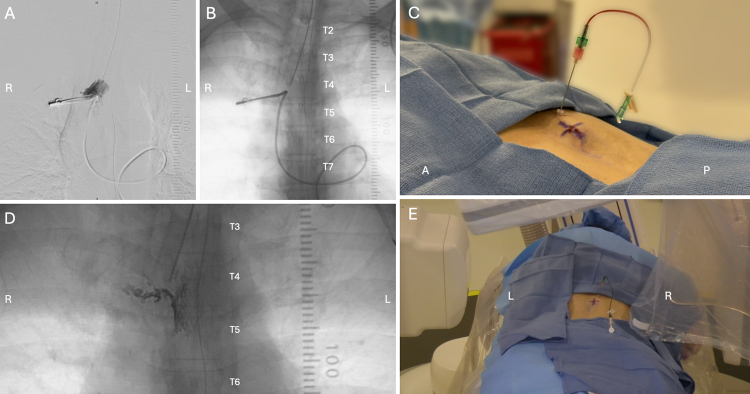

Observations: A 67-year-old male presented with severe positional headaches following minor head trauma. MRI of the brain demonstrated pachymeningeal enhancement, and dynamic CT myelography demonstrated a CVF at the right T4 nerve root. Transvenous CVF embolization was attempted, but there was no suitable target for embolization despite extensive exploration of the azygos, paraspinal, and vertebral veins above and below the fistula. The patient underwent percutaneous puncture of the right T4 paraspinal vein using an 18-gauge Chiba needle under fluoroscopic guidance. Onyx 34 was carefully injected into the CVF under continuous fluoroscopic guidance to embolize the fistula and associated paraspinal venous complex.